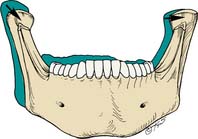

The anterior determinants (Fig. 4-15) are the vertical and horizontal overlaps and the maxillary lingual concavities of the anterior teeth. These can be altered by restorative and orthodontic treatment. A greater vertical overlap causes the direction of mandibular opening to be more vertical during the early phase of protrusive movement and creates a more vertical pathway at the end of the chewing stroke. Increased horizontal overlap allows a more horizontal jaw movement.

Fig. 4-15 Anterior determinants of occlusion. Different incisor relationships with differing horizontal and vertical overlaps (HO and VO) produce different anterior guidance angles (AGA). A, Class I. B, Class II, Division 2 (increased VO; steep AGA). C, Class II, Division 1 (increased HO; flat AGA).